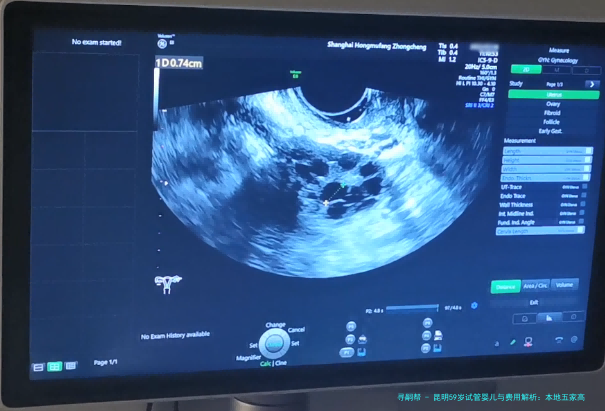

| 阴道B超监测排卵 | 150 | 80 | 110 | 100/次 |